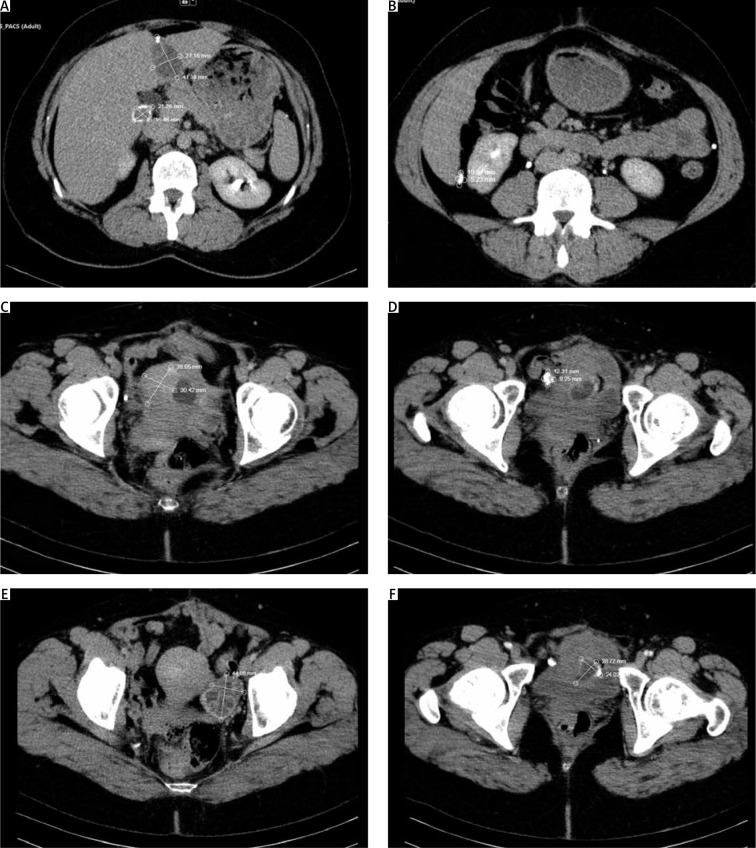

包虫病是由犬带绦虫棘球蚴的幼虫引起的人畜共患疾病。除指甲、毛发和角膜外,它可影响人体的任何器官。它最常累及肝脏、肺、肌肉和骨骼。小盆腔器官受累极为罕见,主要是继发于其他器官的包虫病扩散,卵巢最常受累,其次是子宫。我们接诊了一名 41 岁的白种女性,主诉小盆腔轻微疼痛、沉重,超声检查发现子宫肌瘤。她曾因棘球蚴囊肿接受过两次手术,我们通过计算机断层扫描发现她的肝脏和骨盆中有囊肿形成。我们判定她是棘球蚴病复发,卵巢和子宫都有新的囊肿。于是进行了子宫和附件切除术,一年后没有发现棘球蚴病复发的迹象。如果小盆腔内有包虫形成,就应该想到是棘球蚴病,尤其是如果有证据表明以前曾有过这种疾病的表现。诊断这种疾病对于正确治疗极为重要。子宫受累虽然罕见,但这种可能性不容忽视。

Hydatidosis is a zoonosis caused by the larval form of a cestode of the species Echinococcus granulosus, the canine tapeworm. It can affect any organ of the human body except nails, hair, and cornea. It most often involves the liver, lungs, muscles, and bones. Involvement of organs in the small pelvis is extremely rare, mainly secondary to dissemination of hydatidosis from another organ, and the ovaries are most often involved, followed by the uterus. We present a 41-year-old Caucasian woman with complaints of mild pain, heaviness in the small pelvis, and a fibroid detected by ultrasound examination. She had reported for 2 previous operations for echinococcus cysts, and we found cystic formations in the liver and pelvis by computed tomography. It was decided that it is a recurrence of echinococcosis with a new cyst both in ovary and uterus. A hysterectomy with adnexectomy was performed, and one year later there is no evidence of recurrence of echinococcosis. In the presence of a formation in the small pelvis, one should always think about echinococcosis, especially if there is evidence of previous manifestations of the disease. Diagnosing this disease is extremely important for proper treatment. As rare as uterine involvement is, this possibility should not be overlooked.